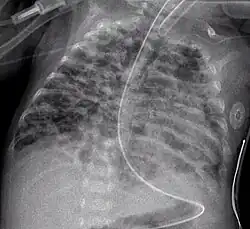

Chest film showing increased opacity in both lungs, indicative of pneumonia -

A chest radiograph showing bronchopulmonary dysplasia. -